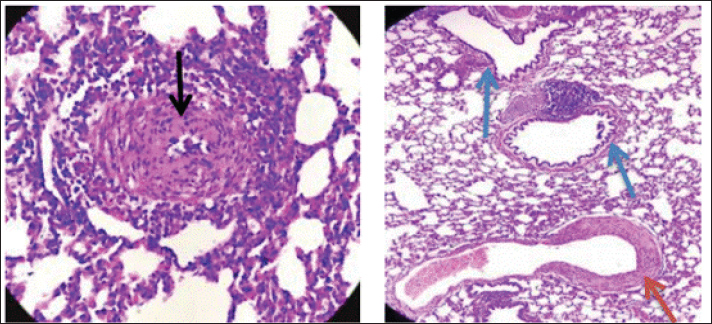

Fig. 6. Group of infected rabbits lung (A) Bronchiols show emphysema aggregation of lymphocytic cell (black arrow)( B) show emphysema structure atelectasis (black arrow) H&E stain 400X and lung H&E stain 200X. Gross examination of sacrificed animals (group of infected rabbits) showed hemorrhage in the upper respiratory tract (Fig. 3). The trachea exhibited a semi-circular hyaline cartilage structure (Fig. 4), and the bronchi branched into left and right bronchioles, consistent with typical mammalian respiratory anatomy. Normal histological details of trachea of control group• Tunica mucosa • Tunica submucosa • Tunica adventitia • C-shaped hyaline cartilage (Fig. 5A) • score lesion of Pathological Changes • Emphysema was observed in 3 out of 5 cases (60%) (Fig. 4). • No pathological changes were seen in 2 cases (40%). • Vascular changes, including congestion, thrombosis, and alveolar hemorrhage, were noted in 10% of affected cases. Comparative morphologyLight microscopy analysis confirmed Gram-negative rods for Raoultella planticola. However, differentiation from Klebsiella spp. was challenging due to morphological similarities (Fig. 2A and B). The histological findings of emphysema and atelectasis align with Blagojević et al. (2018), who described similar structural changes in respiratory infections. The observed hemorrhage and vascular congestion support Castro et al. (2001), who linked these changes to bacterial-induced trauma. The 60% incidence of emphysema suggests that Raoultella planticola primarily induces chronic obstructive pulmonary disease (COPD)-like lesions, differing from Sarhad (2011), who reported fibrinous pleuropneumonia as the dominant pathology. This discrepancy may stem from differences in infection routes or host susceptibility. The short respiratory passage and direct bronchial branching in rabbits (Abdelsalam and Al Sadrani, 2015) likely contribute to higher lung infection rates. Additionally, the similarity between Raoultella and Klebsiella (Alampoondi Venkataramanan et al., 2021) complicates microscopic differentiation, necessitating advanced diagnostic methods like Vitek2.Contrary to Vinshia, J. J., (2024), this study found no fibrinous bronchopneumonia, instead emphasizing edema and congestion (Das and Bhagman, 1997). The reclassification of Raoultella from Klebsiella prior to 2001 further underscores the need for precise microbiological identification (Fig. 8). This study highlights Raoultella planticola's potential to cause respiratory pathology, warranting further investigation into its zoonotic risks.

Fig. 7. The lung is show emphysema group of infected rabbits show moderate fibroplasia of arterioles. (black arrow) and tertiary bronchioles (blue arrow). H&E stain 400X (Castro et al., 2001).

Fig. 8. Group of infected rabbits show(A) arterioles moerate perivascular mononuclear cells infiltration with evidence of vasculitis (black arrow) H&E stain 400X. and B show tertiary bronchioles (blue arrow)with dilated pulmonary arterioles(red arrow) and the lung is show emphysema. H&E stain 100X. DiscussionThis comprehensive examination reveals that when rabbits were given intranasal doses of Raoultella planticola, it led to a mild yet noticeable respiratory infection. The evidence is clear—clinical signs such as dullness, nasal discharge, and watery eyes were apparent. What's more, significant pathological changes were observed, particularly in the lungs, with pulmonary emphysema and atelectasis appearing in 60% of the cases examined. Add to that the striking visible signs of hemorrhage, and it paints quite a concerning picture of the infection's impact. The bacterium's ability to cause disease, boosted by its protective polysaccharide capsule and its close resemblance to Klebsiella species, was convincingly verified using the VITEK2 system. However, when we dive into the histopathological findings, we see hints of emphysema and some intriguing vascular changes that resonate with certain literature; yet, there’s a twist—this evidence points more toward a COPD-like condition rather than the fibrinous pneumonia that's been noted in other studies. Moreover, the antimicrobial susceptibility profile painted a complex picture, revealing varying degrees of resistance that certainly pose difficulties for treatment. All in all, these findings affirm that R. planticola can trigger respiratory issues through the nasal route, shedding light on the pressing need for accurate diagnostics and further exploration into its virulence and potential to jump from animals to humans. ConclusionRaoultella planticola are very similar in phenotype to Klebsiella spp. in epidemiology and the clinical signs in respiratory infection of rabbit. The R. planticola causes mild to moderate emphysema in local rabbit. The previous difficulties in the identification of R.planticola and known of more detailed may needed PCR technique to confirm diagnosis. Intranasal infection was the effective route and the main pathological changes observed in the respiratory system characterized by presence of atelectasis indicated of emphysema. Further studies of molecular sequences are required. AcknowledgmentsThe authors extend their sincere thanks to the Faculty of Veterinary Medicine/the University of Kufa for their unwavering support. The authors also intensely appreciate the contributions of the veterinarians and staff at the Veterinary Hospital Laboratory and Wasit Abattoir for their technical support and collaboration in sample collection and analysis. Authors' ContributionAll listed authors have made significant intellectual and academic contributions to this study. Each author has reviewed and approved the final manuscript for publication. Competing interestsThere are no conflicts of interest numerous of the authors concerning the publishing this manuscript. FundingNone. Data availabilityAll the datasets formed or examined during this work are included in the publication. ReferenceAbdelsalam, E.B. and Al Sadrani, A.A. 2015. Incidental findings of pathological significance in pneumonic lungs of sheep in Al Qassim Area, Kingdom of Saudi Arabia: an abattoir survey. Comparative. Clin. Pathol. 24, 951–955. Alampoondi Venkataramanan, S.V., George, L., Sahu, K.K. and Abraham, G.M. 2021. A 5-Year Retrospective analysis of Raoultella planticola bacteriuria. InfectDrug. Resist. 1989, 1989–2001. Bagley, S.T., Seidler, R.J. and Brenner, D.J. 1981. Klebsiella planticola sp. nov.: a new species of Enterobacteriaceae found primarily in nonclinical environments. Curr. Microbiol. 6(6), 105–109. Bancroft, J.D., Layton, C. and Suvarna, S.K. 2013. Bancroft's theory and practice of histological techniques. Churchill Livingstone Elsevier. Nottingham, UK: Elsevier. Blagojević, M., Božičković, I., Ušćebrka, G., Lozanče, O., Đorđević, M., Zorić, Z. and Nešić, I. 2018. Anatomical and histological characteristics of the lungs in the ground squirrel (Spermophilus citellus). Acta Veterinaria Hungarica 66(2), 165–176. Castro, P., Chiu, P., Kremenek, T. and Muntz, R. A probabilistic room location service for wireless networked environments. In Ubicomp 2001: Ubiquitous Computing: International Conference Atlanta Georgia, USA, September 30–October 2, 2001 Proceedings 3,2001 Springer Berlin Heidelberg, Atlanta, Georgia, 3, pp 18–34. Chun, S., Yun, J.W., Huh, H.J. and Lee, N.Y. 2014. Low virulence? Clinical characteristics of Raoultella planticola bacteremia. Infection 42, 899–904. Das, B., Rao, A.R. and Madhubala, R. 1997. Difluoromethylornithine antagonizes taxol cytotoxicity in MCF-7 human breast cancer cells. Oncol. Res. Featuring. PreClin. Clin. Cancer. Therapeutics. 9(11-12), 565–572. Demiray, T., Koroglu, M., Ozbek, A. and Altindis, M. 2017. A rare cause of infection, Raoultella planticola: emerging threat and new reservoir for carbapenem resistance. Infection 44, 713–717. enters for Disease Control and Prevention. (2010). Klebsiella pneumoniae in healthcare settings. Available via https://www. cdc. gov/hai/organisms/klebsiella/klebsiella. html (accessed: 2019, May 20). Eroschenko, V.P. and Di Fiore, M.S. 2013. DiFiore's atlas of histology with functional correlations. Philadelphia, PA: Lippincott Williams & Wilkins, pp: 263–6. Freney, J., Fleurette, J., Gruer, L. D., Desmonceaux, M., Gavini, F., and Leclerc, H. 1984. Klebsiella trevisanii colonisation and septicaemia. Georgi. and Anderson. 1975. The Cornell Veterinarian. Cornell Vet. 66, 309–323. Ghoshal, N.G. and Bal, H.S. 1989. Comparative morphology of the stomach of some laboratory mammals. Lab. Animals 23(1), 21–29. Harcourt-Brown, F. 2002. Textbook of rabbit medicine. Elsevier Health Sciences.. Howell, C. and Fakhoury, J. 2017. A case of Raoultella planticola causing a urinary tract infection in a pediatric patient. Translational Pediatrics 6(2), 102. Jiménez Castro, D., Pérez-Rodríguez, E., Montaner, L., Flores, J. and Díaz Nuevo, G. 2001. Diagnostic value of D dimer in pulmonary embolism and pneumonia. Respiration 68(4), 371–375. Luna, L.G. 1968. Manual of histologic staining methods of the Armed Forces Institute of Pathology. In Manual of histologic staining methods of the Armed Forces Institute of Pathology. McGraw-Hill, New York: NY, pp: xii–258. Podschun, R., Acktun, H., Okpara, J., Linderkamp, O., Ullmann, U. and Borneff-Lipp, M. 1998. Isolation of Klebsiella planticola from newborns in a neonatal ward. J. Clin. Microbiol. 36(8), 2331–2332. Ramchandani, V.A., Bosron, W.F. and Li, T.K. 2001. Research advances in ethanol metabolism. Pathologie. Biologie. 49(9), 676–682. Sahu, K., Sherif, A. and Davaro, R. 2020. A rare cause of cellulitis: photobacterium damselae. J. Microsc. Ultrastructure 8(1), 25–26. Sarhad, A.N.S. 2011. Pathogenesis of Pasteurella multocida in Rabbits by Intra-nasal and Intra-ocular infection. Iraqi. J. Vet. Med. 35(1), 42–53. Sękowska, A. 2017. Raoultella spp.—clinical significance, infections and susceptibility to antibiotics. Folia. Microbiologica. 62(3), 221–227. Suvarna, S.K., Layton, C. and Bancroft, J.D. 2019. Theory and practice of histological techniqueseighth. Oxford, UK: Elsevier Health Sci. Vinshia, J.J., Padmavathy, K. and Sathyapriya, B. 2024. Comparison of the VITEK® 2 system with conventional methods for species identification and antimicrobial susceptibility pattern of staphylococcal carrier isolates. Int. Res. J. Multidisciplinary. Scope. (IRJMS). 5(2), 940–948. Woodman, C.B., Collins, S., Winter, H., Bailey, A., Ellis, J., Prior, P., Yates, M., Rollason, T.P. and Young, L.S. 2001. Natural history of cervical human papillomavirus infection in young women: a longitudinal cohort study. Lancet 357(9271), 1831–1836. | ||